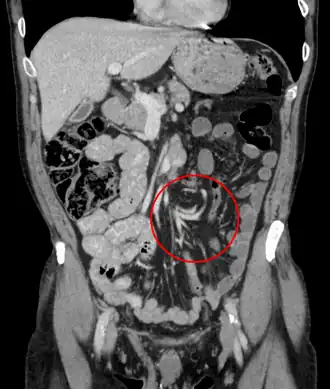

Per volvolo (dal latino volvere: arrotolare, avvolgere intorno) si intende una grave patologia chirurgica, non molto frequente, caratterizzata dalla torsione su sé stesso di un viscere tubulare o di un suo segmento. Colpisce alcuni distretti dell'apparato digerente, in particolare il sigma, perché più predisposto in quanto mobile e a volte particolarmente lungo (dolicosigma) e poi, in ordine decrescente le anse intestinali, la flessura splenica del colon e ancor più raramente lo stomaco.

La presenza di un volvolo comporta un'occlusione intestinale e una necrosi ischemica dell'organo per strozzamento dei vasi sanguigni contenuti nel suo mesentere e si manifesta in genere con i segni di un'occlusione meccanica complicata.

La diagnosi è legata al quadro clinico che per la sua drammaticità (dolore intenso e segni di peritonite) assume i caratteri propri di un addome acuto, situazione che impone un intervento laparotomico urgente. Possono servire a confortare la diagnosi le indagini radiografiche, esame diretto dell'addome e un esame TC dell'addome e della pelvi, che servono a evidenziare in generale il grado e il livello dell'occlusione e in alcuni casi possono permettere anche l'individuazione della causa (segni particolari del volvolo) e quelle ecografiche che possono evidenziare una raccolta di liquido endoperitoneale.